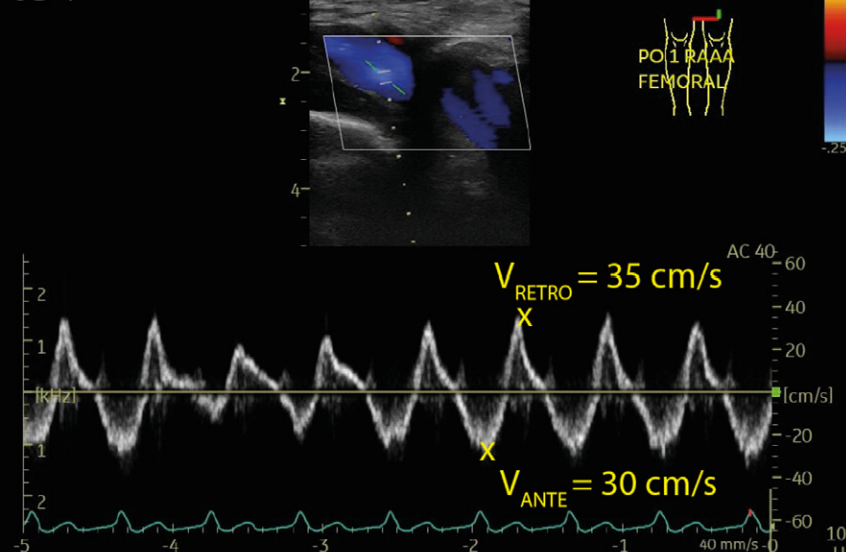

Antegrade femoral vein flow velocity representing vein flow from the periphery to the right side of the heart is 30 cm/s, whereas retrograde velocity of 35 cm/s represents systolic flow reversal, right ventricular dysfunction

Femoral vein Doppler pulsatility in venous congestion Serial femoral vein Doppler in a patient with severe venous congestion, and after 4 days of diuresis 1 . Femoral vein flow is biphasic with an important retrograde component